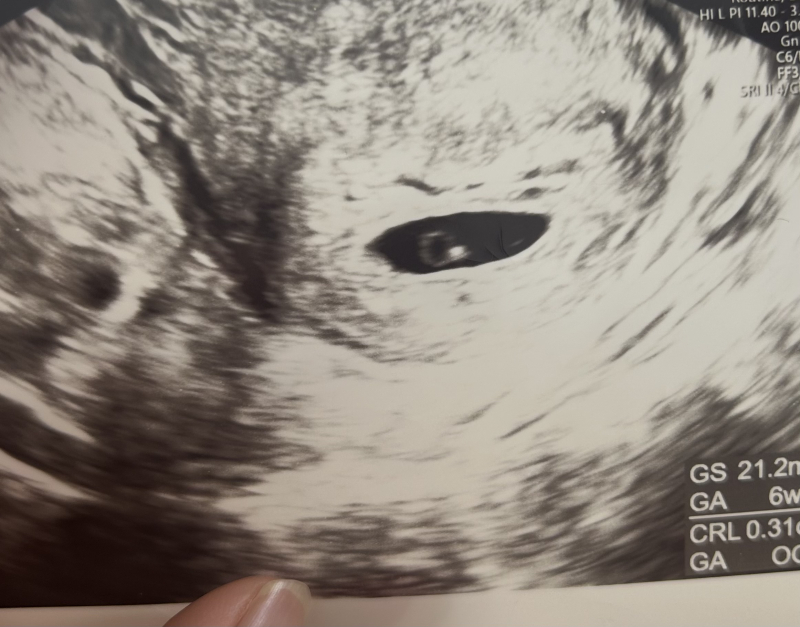

現在妊娠6週になります。

出血したその日に、病院を受診し診てもらいましたが胎嚢、赤ちゃんも確認でき元気でした。

本当に絨毛膜下血腫か載せているエコーを見てご意見いただけると嬉しいです。

エコーのお写真からですと、実際に拝見しているわけではないので、なかなかはっきりとしたことは明言できませんが、絨毛膜下血腫の場合には、血腫の出来ている位置や大きさによっても、安静度や期間が異なるかと思います。絨毛膜下血腫の場合には、子宮の中の一部分に出血が溜まってしまっている状態であり、その溜まっている出血が排出されたり、吸収されたりすることで小さくなってきます。ですので、出血が溜まっている間は、断続的に出血する可能性があります。この時期には、なかなか積極的な治療をすることも難しく、とにかく安静にしていただき、血腫が小さくなるのを待つという方法になることが多いように思います。私も3人目の妊娠初期に絨毛膜下血腫になり、しばらく安静にしていました。naさんの血腫がどの程度の大きさで、どの位置にあるか詳細は分からないですが、血腫ができていても、次第に小さくなってくれば、問題なく出産される方もたくさんいらっしゃいますよ。今はとてもご心配と思いますが、可能な範囲で安静にしていただき、お腹の痛みがあったり、出血が増えたりしないかをよくみていただけるといいと思いますよ。